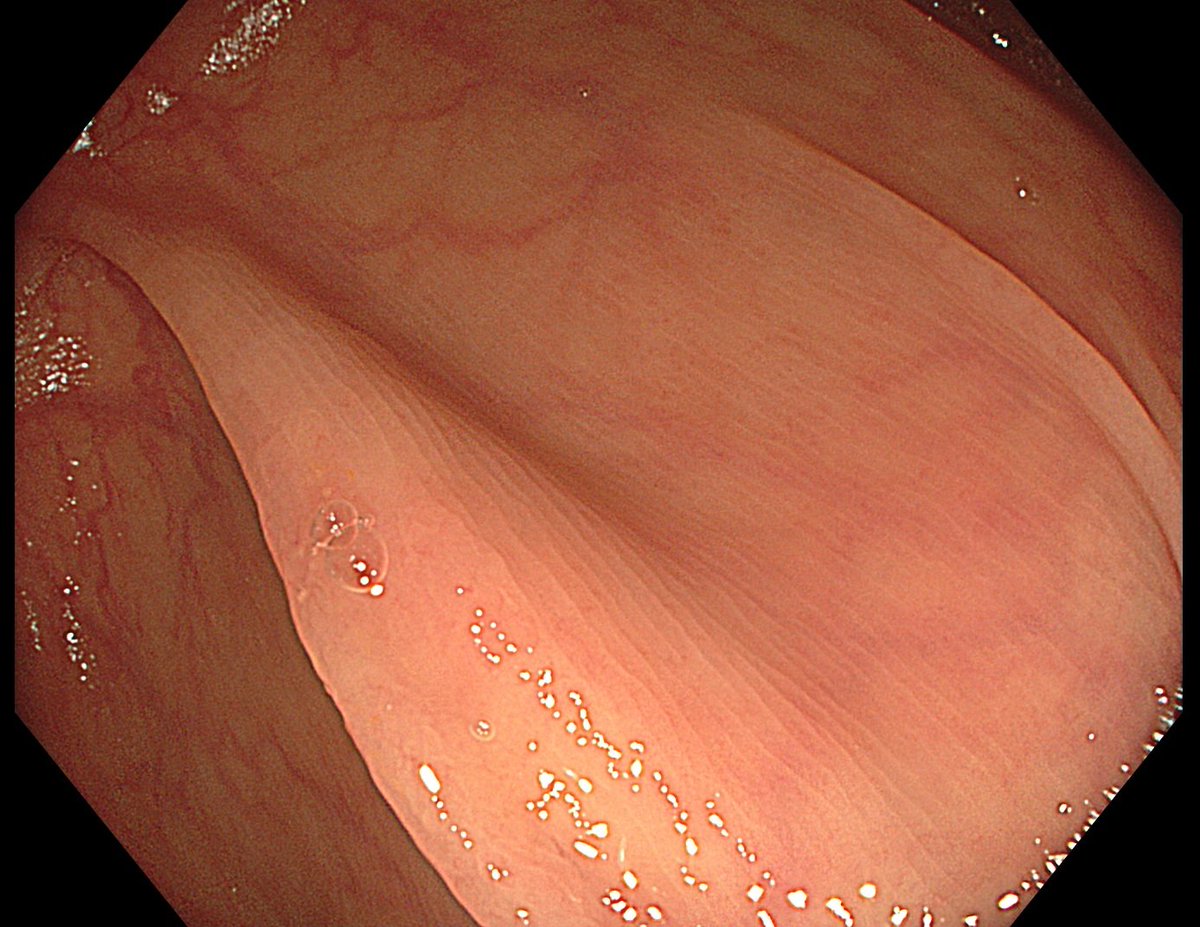

1. Antrum, low grade dysplasia. Removed via ESD. Specimen 43x32mm / dysplasia 20x13mm. R0